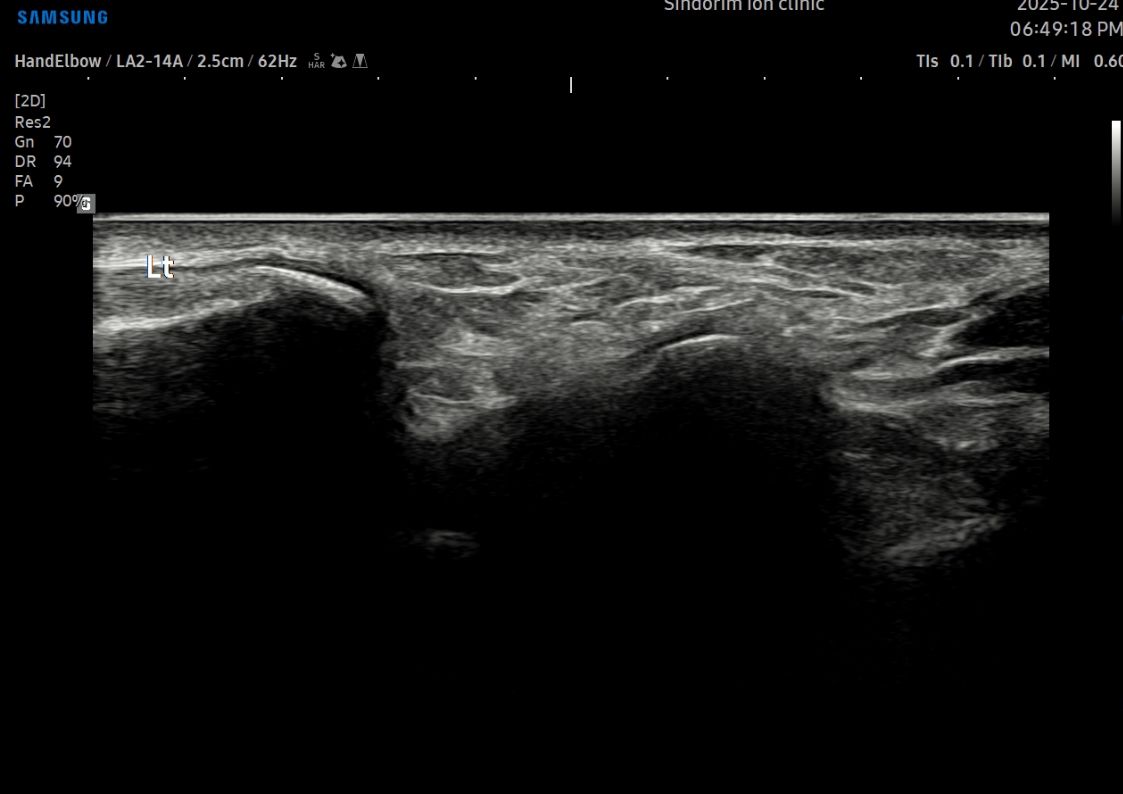

- 치료기간 : 25 . 5 . 7 ~ 25 . 8 .12

- 치료횟수 : 4cycle(20) 회

치료전

치료후